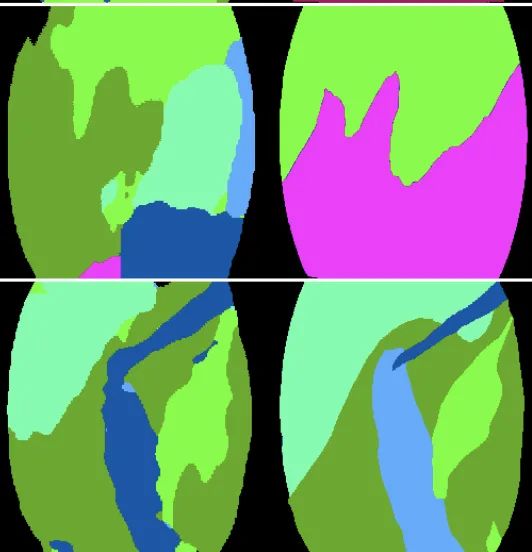

FASCICLE 小腿肌肉超声数据集

数据集链接:http://m6z.cn/631rex

FAscicle 小腿肌肉超声数据集是一个由 812 幅小腿肌肉超声图像组成的数据集,用于分析肌肉弱点并预防受伤。该数据集在文章 AW-Net:B 型超声图像上的自动肌肉结构分析以预防伤害中进行了介绍。它结合了由 Ryan Cunningham 等人发表的两篇文章“使用卷积、残差和反卷积神经网络从 B 模式超声图像中估计全区域骨骼肌纤维方向”提供的数据集。和 Neil Cronin 发表的“使用深度学习对肌肉骨骼超声图像进行自动分析”,并附有补充注释。

该 zip 文件包含两个数据集,分别分为两个由其作者命名的文件夹。每个数据集的每个图像都有一个匹配的分束分割掩码和一个可按名称识别的腱膜分割掩码。